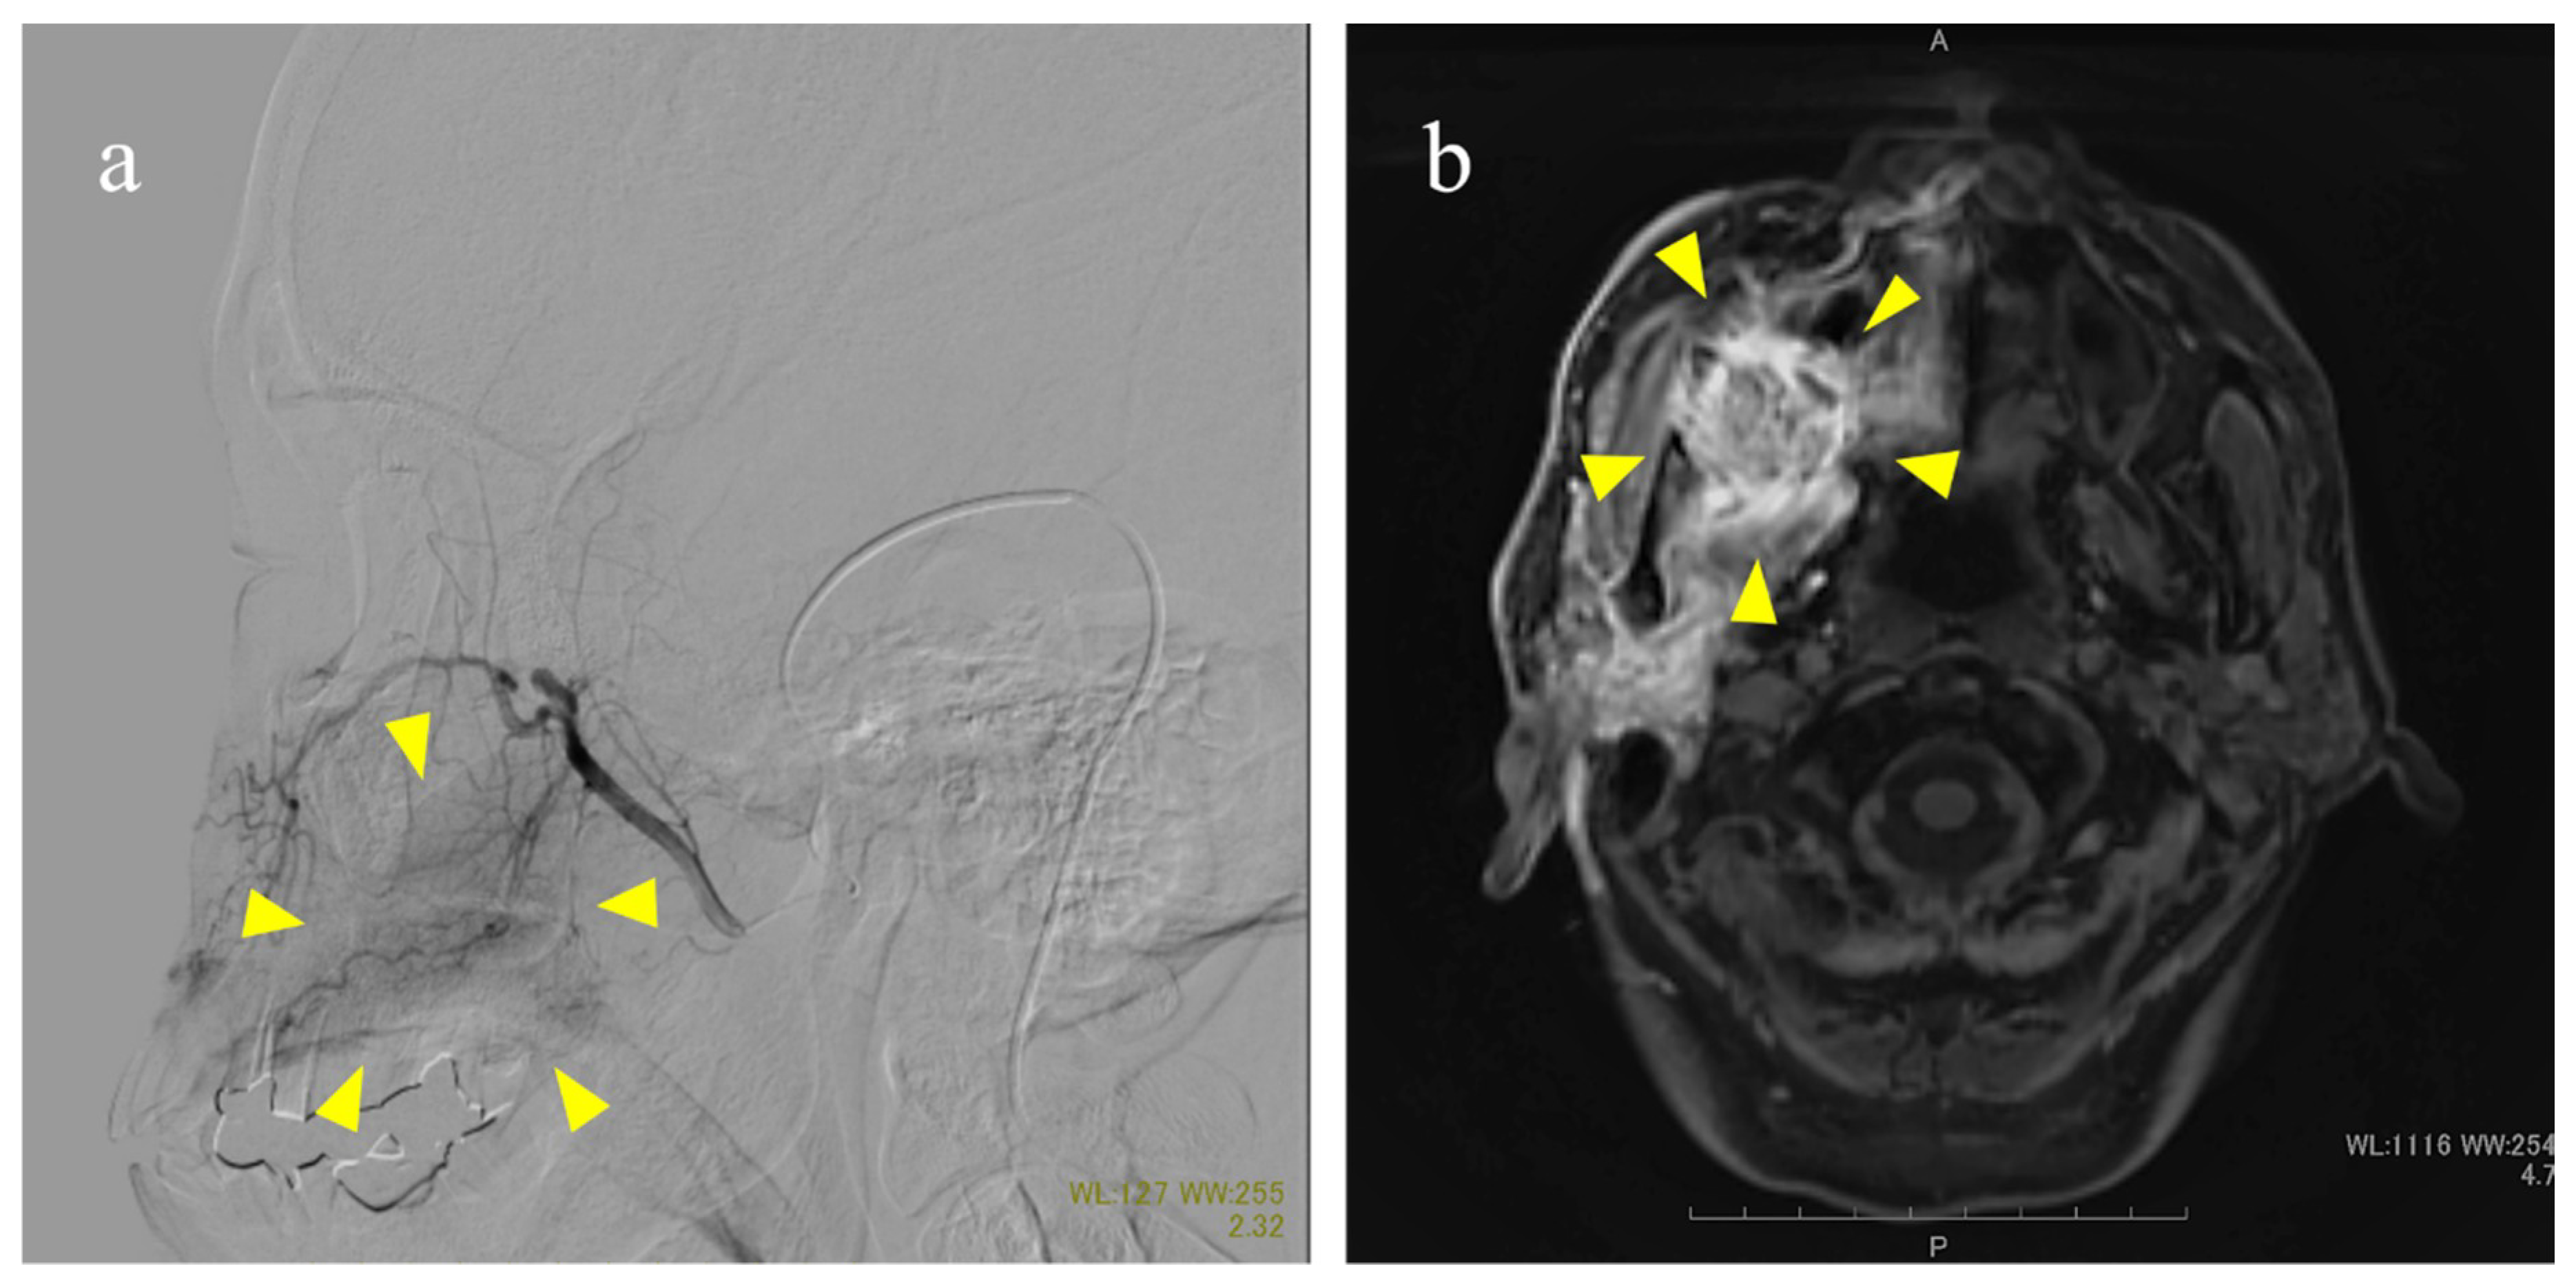

- Nakamura, T.; Fuwa, N.; Takayama, K.; Tomoda, T.; Takada, A.; Makita, C.; Shiomi, M.; Yokouchi, J.; Watanabe, K. A new method using MRI to delineate areas of head and neck cancer targeted by intra-arterial infusion via a superficial temporal artery. Oral Oncol. 2011, 47, 387–390. [Google Scholar] [CrossRef] [PubMed]